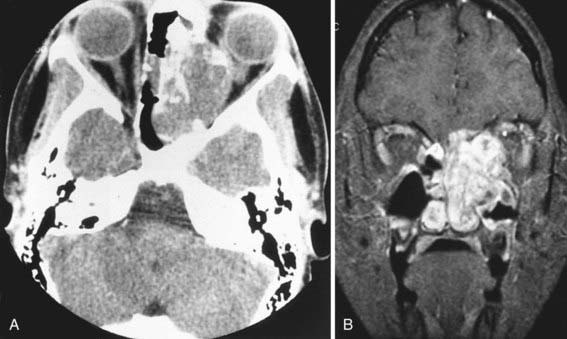

Symptoms and signs of rhabdomyosarcoma (Chapter 494) originating in the middle ear or ear canal include a mass or polyp in the middle ear or ear canal, bleeding from the ear, otorrhea, otalgia, facial paralysis, and hearing loss. Other cranial nerves also may be involved. Diagnosis is based on biopsy, but the extent of disease is determined by both CT and MRI of the temporal and facial bones, skull base, and brain (Fig. 635-1). Management usually involves a combination of chemotherapy, radiation, and surgery.

Figure 635-1 Rhabdomyosarcoma in a 2 yr old child presenting with a large mass in the nose. A, CT scan of the head shows destruction of the nose and lamina papyracea; a large soft tissue mass is present. B, MRI shows enhancement of the mass.

(From Slovis T, editor: Caffey’s pediatric diagnostic imaging, ed 11, Philadelphia, 2008, Mosby, p 560.)